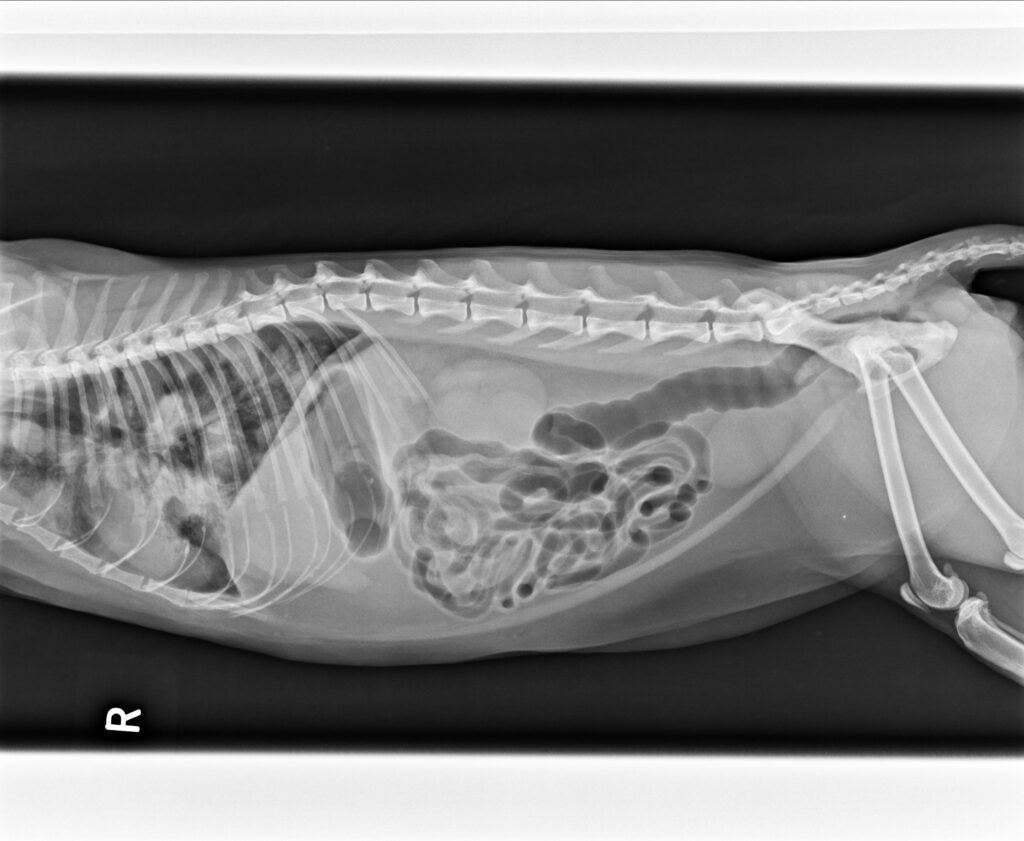

2023/5/11,一位街貓5.3公斤,3歲的橘貓因為很喘被附近的愛心人士帶來就診。愛心人士表示平時橘貓在他們家附近閒晃,他們就是定時餵食飼料,最近沒看到橘貓,再看到橘貓時就是一副很喘的樣子來找他們。愛心人士擔心之餘,經人介紹前來看診;在緊急為橘貓照完X光後,果然是罹患了肺炎。

胸腔X光1-3張見到瀰漫性結節團塊浸潤